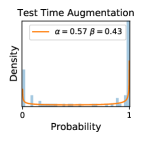

5.1 Distribution of Uncertainty Scores

Distribution of Uncertainty Scores Across Different Severity Levels As explained in Section 3, each uncertainty metric essentially defines an order/ranking among the data points. We conducted an analysis to better understand what data will be assigned high uncertainty under a particular uncertainty metric . Picking out the highest ranked data points (), we calculated the ratio of data points from each SL. Figure 4 summarizes the results as box plots for the Kaggle-DR and the Messidor-2 datasets; additional detailed statistics can be found in Table S.1 in the supplementary materials. From the plot and table, SL1 & SL2 examples account for a higher proportion among the top-ranked uncertain examples across the three ensemble methods. This finding matches our intuition that incipient disease examples (SL1 & SL2) are more likely to be considered uncertain by ensemble methods due to their ambiguity.

Comparing the three ensemble methods in Figure 4, the stacking ensemble method has the highest ratios of SL1 & SL2 data among the high-uncertainty examples it identified under both mean and var. TTA showed slightly better performance than MC-dropout but still falls behind the stacking ensemble method. Considering the fact that SL0 examples accounted for the majority of the dataset, the stacking ensemble method was much more precise (specific) in selecting truly ambiguous data points that were difficult to classify. From Figure 3, we can also see that the stacking ensemble method greatly outperformed the other two methods in finding false negatives under both mean and var uncertainty metrics.

In contrast, the MC-dropout method showed the worst overall performance among the three, as it can be seen from the high ratios of SL0 examples among the uncertain negatives in Figure 4. The histograms in Figure 2 provides another perspective to look into the phenomenon, where a decent proportion of MC-dropout model’s predictions on SL0 inputs entailed low confidence (far from 0 or 1), which from another angle explained why MC-dropout was less specific in terms of lower FNP; many no-DR inputs (i.e. SL0) were erroneously assigned high uncertainty by MC-dropout models.

It is still an open question why the evaluated MC-dropout networks signaled relatively high uncertainty on SL0 & SL3 & SL4 data that are less likely to be ambiguous. We conjecture that much of the “uncertainty” indicated by disagreement among test-time dropout samples actually reflects the stochastic nature of dropout networks rather than the real decision uncertainty associated with the data. It is worth noting that the MC-dropout model we evaluated was not weak per se; they all achieved above Area Under Curve (AUC) scores on test sets. The weakness of individual test-time samples (which explains their low-confidence predictions on SL0 & SL3 & SL4) might have been hidden when they are aggregated into an ensemble—a well-known advantage of ensemble learning. Our results suggested that the uncertainty information given by implicit ensemble methods such as MC-dropout and TTA might not be as reliable as that from explicit ensemble approaches (e.g., stacking ensembles). Similar findings on MC-dropout can be found in some previous papers [1].